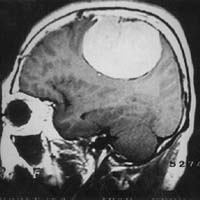

<¾È¿ÍºÎ

³ú¼ö¸·Á¾>

<¼ö¼ú

Àü>

<¼ö¼ú ÈÄ>

¿ìÃø

½Ã·Â°¨¼Ò¿Í ¾È±¸¿îµ¿Àå¾Ö¸¦ º¸ÀÌ´ø ȯÀÚ¿¡¼

¹ß°ßµÈ ¾È¿ÍºÎ ¼ö¸·Á¾ ³úMRI ¼Ò°ß(¼ö¼úÀûÄ¡·á·Î

ÀüÀûÃâµÇ¾ú´Ù)